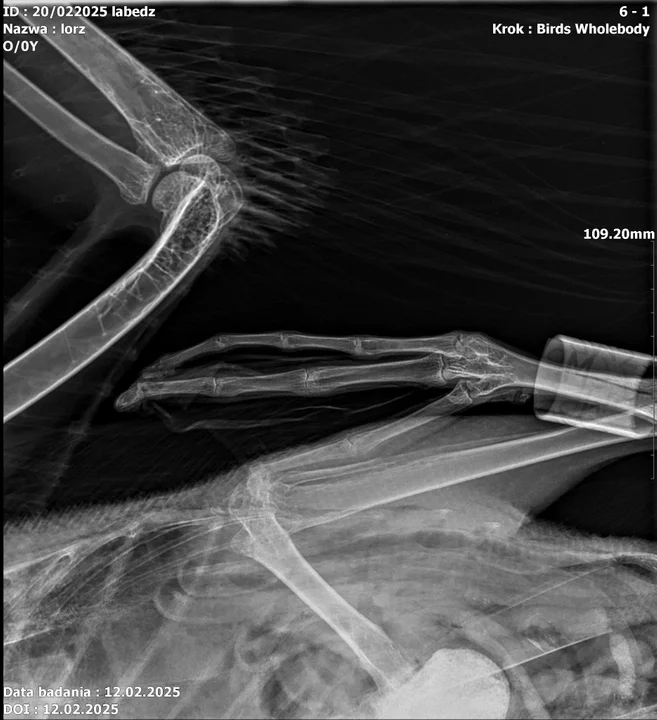

Facebook

Trwają badania ptaka, jednak jak zapewnia w rozmowie z portalem Trybunalski pl. Paweł Kowalski z Nadleśnictwa w Piotrkowie, jego stan jest stabilny.